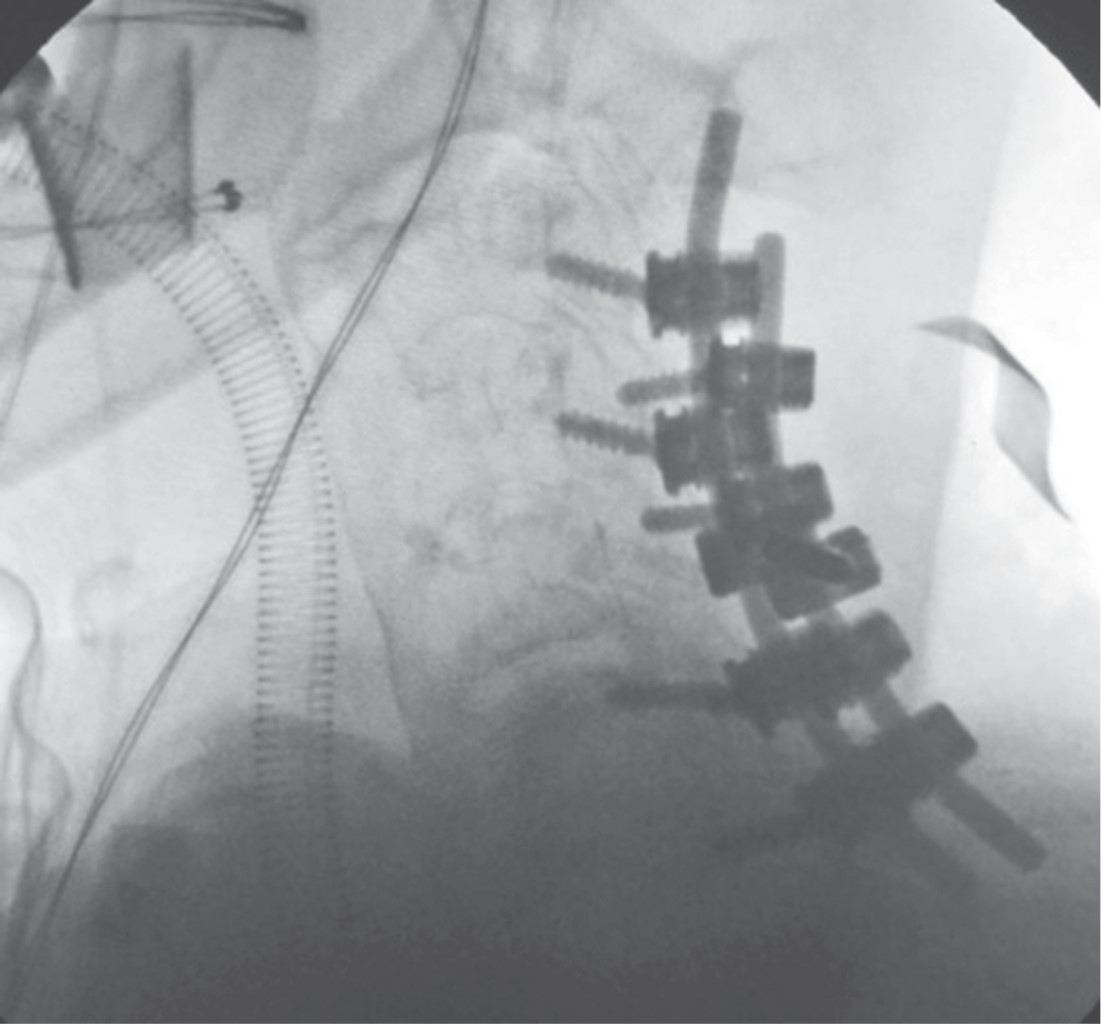

Diffuse idiopathic idiopathic skeletal hyperostosis (DISH), or Forestier's disease is a rare disease of unknown etiology. It is a systemic condition in which ossification of the anterolateral sides of at least four contiguous bodies, calcification of ligaments and entheses develops and is accompanied by spinal pain predominantly in the thoracic spine. In this case report we present a 70-year-old female patient presenting with DISH with complete spinal cord injury from c7 to distal on ASIA A scale following a fall from her own plane of support managed surgically with posterior cervical approach and instrumentation of lateral masses and decompression with good clinical evolution and partial clinical recovery to ASIA C.

Figure 4